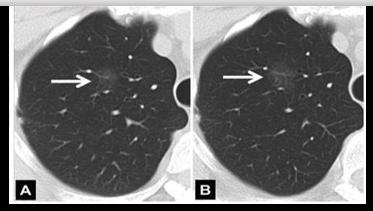

7mm磨玻璃结节,定期复查,20个月后CT发现结节长大,手术切除,病理证实为微浸润腺癌。因此,唐教授特意提醒大家,虽然磨玻璃结节50%以上为恶性,但也无需过分恐慌,因为其生长速度很慢,绝大多数小于7mm的磨玻璃结节均属很早期,可以定期复查,如果发现结节长大或密度增大,再手术切除。

磨玻璃结节,定期复查,5年均未见明显变化,继续随访。对于这种不生长的情况,专业称为“休眠”,休眠状态通常不需要手术治疗,患者可以带结节生活,因此,是否需要手术需要医生根据实际情况做专业判断。

8mm磨玻璃结节,定期随访,CT发现结节实性成分增多,手术切除,病理为腺癌。

唐小军教授提到,直径≤8mm的结节需定期随访,是否需要手术要根据随访结果而定。对此,唐小军教授展示了几个具体的病例进行说明: